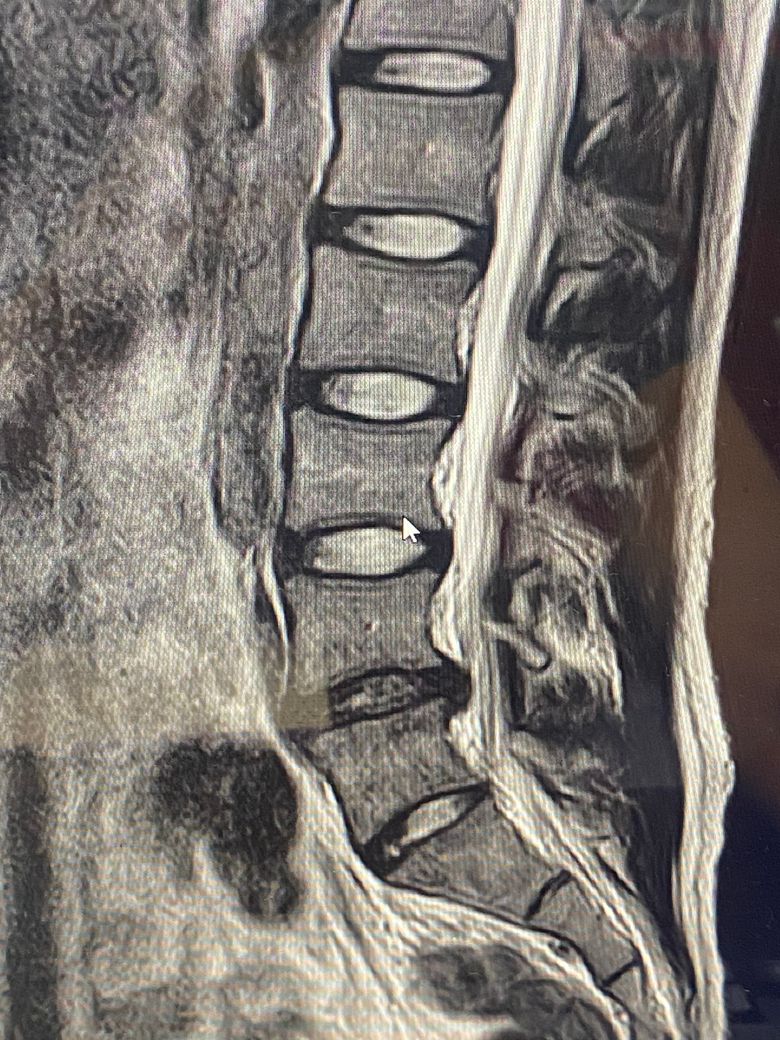

• 3번 째 사진

MRI는 3컷만으로 평가할수 없지만 현 상태상 허리 디스크 탈출증이 의심됩니다.

• MRI 단면 몇 장으로 정확하게 상태를 평가하기는 어렵지만 요추 4번의 디스크 돌출 및 그로 인한 척수의 눌림이 발생한 것으로 사료됩니다. 방사통이 있는 상태에서는 심한 운동을 할 때에 디스크 증상을 오히려 악화시킬 수 있기 때문에 현재 상태에서 바로 헬스를 하시기 보다는 식이요법과 걷거나 가볍게 뛰는 정도의 운동을 통해서 체중 감량을 하시고 통증에서 자유로워 지면 그 때에 피트니스나 필라테스 등을 통해서 직립근 등 코어 근육을 강화해주시는 것을 추천드립니다.